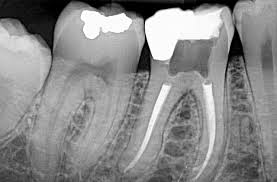

Una radiografía periapical es un tipo de imagen dental que muestra en detalle uno o dos dientes completos, desde la corona hasta la raíz y el hueso circundante. Se utiliza comúnmente para:

• Detectar caries dentales debajo de las encías.

• Observar la salud del hueso que sostiene el diente.

• Diagnosticar abscesos, infecciones o quistes.

• Evaluar el estado de los tratamientos de conducto.

• Examinar dientes fracturados o con problemas periodontales.